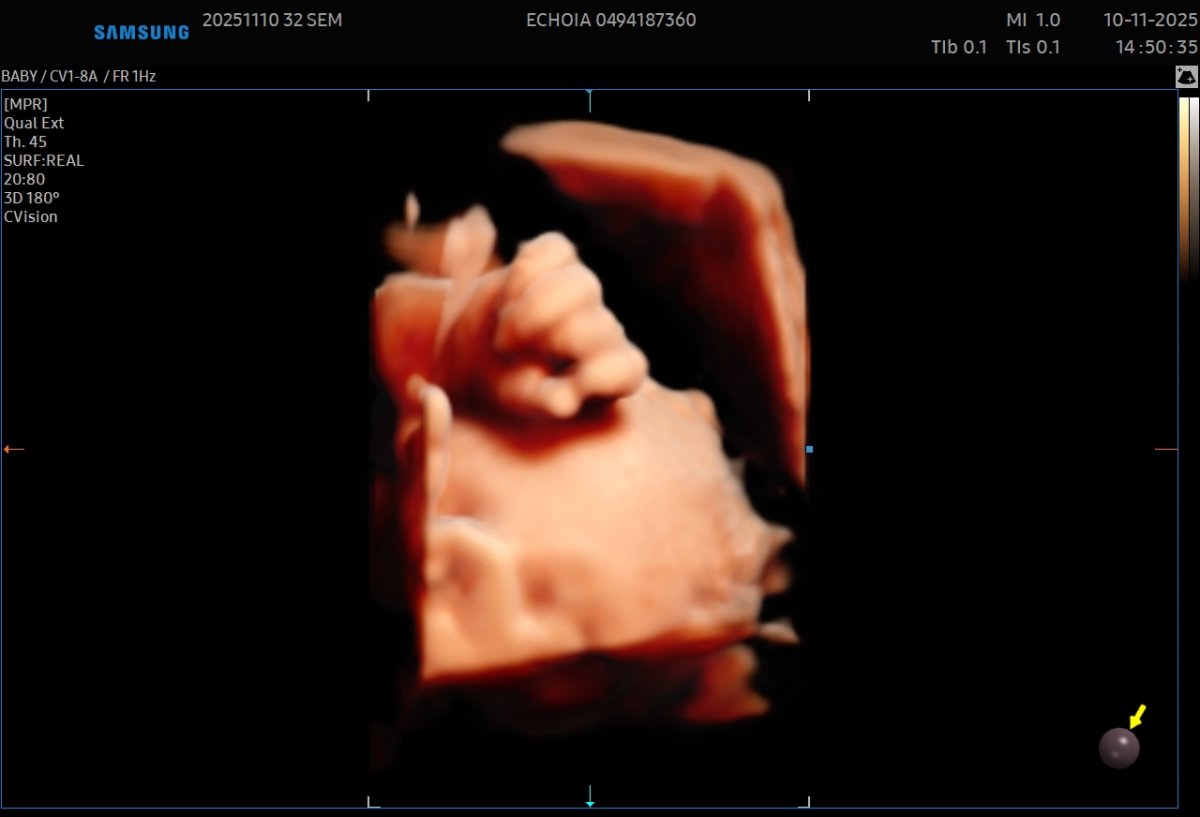

Gallerie de photos